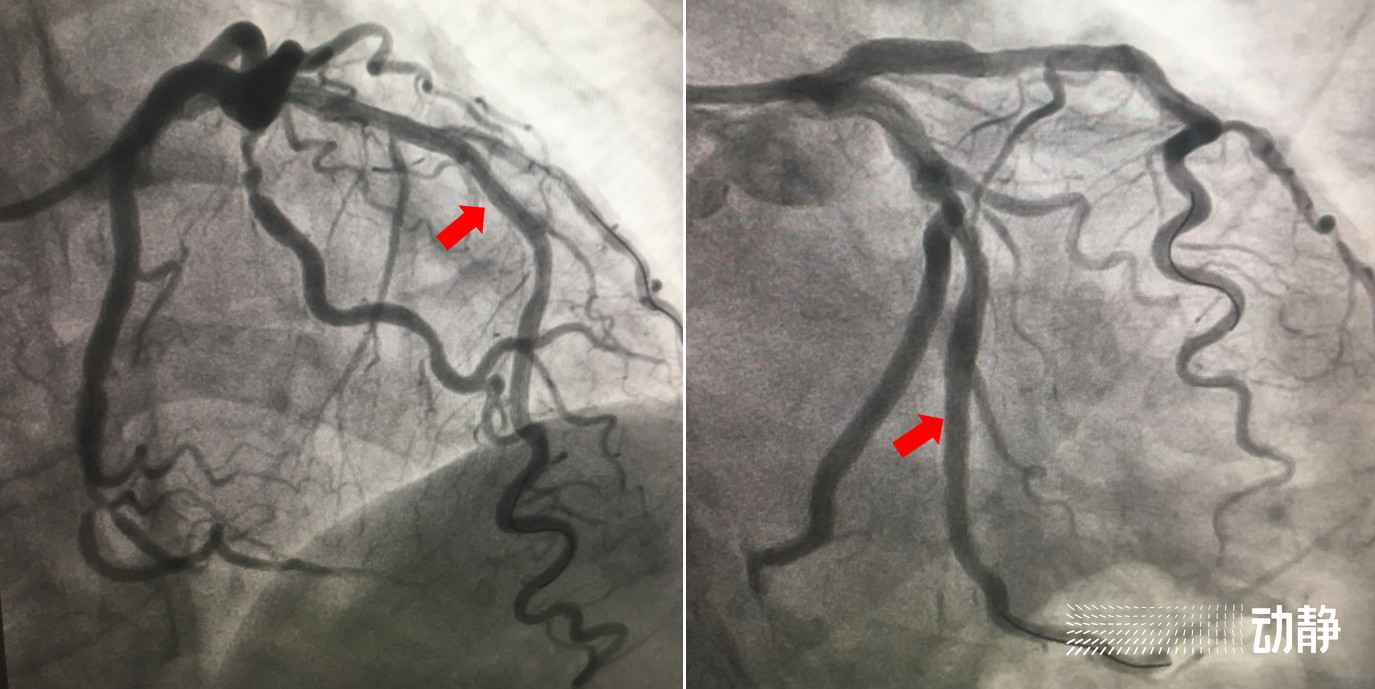

在专家团队的默契配合下,仅1小时左右,就成功同时在夏婆婆的前降支血管及回旋支血管各植入1枚支架。陈游洲说:“对于夏婆婆这个病例来说,我们的手术大大节约了时间。考虑到她的身体条件,我们采用了恰当的造影剂用量,支架尺寸准确,医生操作准确,都为缩短手术时间、减轻患者痛苦做出了贡献。”